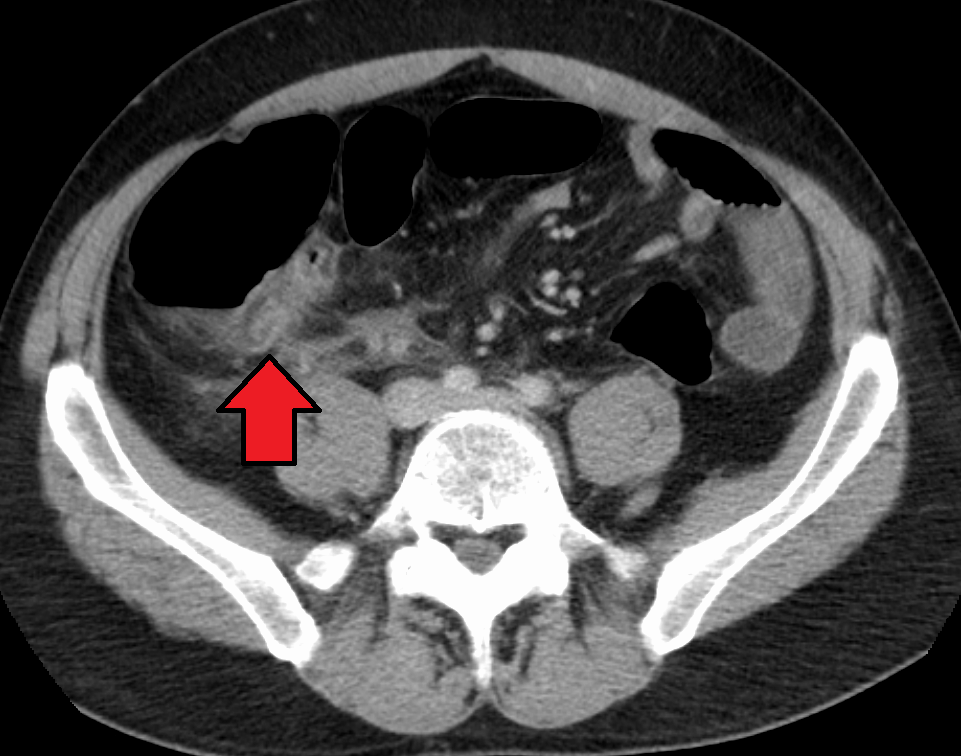

CT 스캔은 급성 충수염을 진단하는데 사용된다.[36] 의사는 환자의 병력과 증상을 평가하고, 신체 검사를 시행하며, 검사실 및 영상 검사를 모두 주문한다. 비전형적인 증상을 보이는 경우에는 초음파나 CT 스캔과 같은 영상 검사가 필요하다.[12] 소아는 방사선 노출 위험 때문에 초음파 검사를 우선적으로 시행하며, 결과가 불확실한 경우에만 CT 스캔을 추가로 시행한다.[54][55][56] 성인 및 청소년의 경우 CT 스캔이 초음파 검사보다 더 정확하며, 민감도 94%, 특이도 95%를 보인다. 반면 초음파 검사는 민감도 86%, 특이도 81%이다.[57]복부 초음파 검사, 특히 도플러 초음파는 특히 소아에게서 충수염 진단에 유용하다. 초음파 검사에서는 오른쪽 장골와에서 액체 저류, 컬러 도플러 사용 시 혈류 증가, 충수의 비압착성 등이 관찰된다. 급성 충수염의 다른 징후로는 충수 주변의 에코성 장간막 지방, 충수 결석의 음향 그림자 등이 있다.[58] 약 5%의 경우, 장골와 초음파 검사에서 이상이 발견되지 않지만, 이는 초기 충수염이거나 지방과 장내 가스로 인해 충수 확인이 어려운 성인에게서 흔하게 나타난다. 숙련된 검사자는 초음파 영상을 통해 충수염과 유사한 증상을 보이는 림프절 염증, 난소 또는 나팔관 문제 등을 구별할 수 있다.[60] 초음파 검사는 방사선과나 응급 의학 전문의가 시행할 수 있다.

충수염 진단은 충수 크기가 가장 중요하며, 6mm 이상이면 민감도와 특이도가 모두 95%이다.[65] 그러나 충수가 분변 물질로 채워져 팽창된 경우에는 진단이 어려울 수 있다.[66] 이 경우 초음파 검사가 유용하며, 주변 장에 비해 벽의 조영 증강, 주변 지방 염증 등의 특징으로 진단을 돕는다. 심한 경우 농성 염증, 고름집, 고름이나 장 내용물 누출로 인한 골반 내 액체 층이 관찰될 수 있다. 마른 환자는 지방 부족으로 충수와 주변 염증 관찰이 어려울 수 있다.[66]

CT 검사에서 충수 부종이나 주변 지방 조직 농도 상승이 관찰되며, 조영제 사용 시 민감도와 특이도가 모두 98%로 정확도가 높다. 최신 초음파 검사 장비는 맹장 형태 평가에 유용하지만, 맹장 위치나 장비, 검사자 숙련도에 따라 진단이 어려울 수 있다. 최근 소아 충수염 진단에서 컴퓨터 단층 촬영(CT) 검사는 감소하고 초음파 검사는 증가했지만, 임상 경과에는 변화가 없다는 보고가 있다.[126]